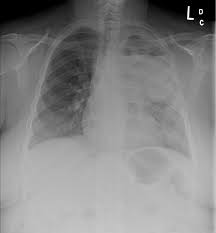

What Does Lung Cancer Mean In Spanish : Adrenal Conditions What Are Adrenal Glands Symptoms Treatment Diagnosis Ucla Endocrine Center Los Angeles Ca : Lung cancer begins in the lungs and may spread to lymph nodes or other organs in the body, such as the brain.. Lung cancers typically start in the cells lining the bronchi and parts of the lung such as the bronchioles or alveoli. Slcg means spanish lung cancer group. A thin lining layer called the pleura surrounds the lungs. A cancerous (malignant) tumour is a group of cancer cells that can grow into and destroy nearby tissue. Lung cancer, also known as lung carcinoma, is a malignant lung tumor characterized by uncontrolled cell growth in tissues of the lung.

Lung cancer is a disease in which malignant (or dangerous) cells form in the tissue of the lungs. Sometimes lung cancer does not cause any signs or symptoms. S what does that mean? The pleura protects your lungs and helps them slide back and forth against the chest wall as they expand and contract during breathing. Lung cancer prevention approaches include avoiding exposure to risk factors like tobacco smoke, radon, radiation, asbestos, and other substances. Lung cancer, also known as lung carcinoma, is a malignant lung tumor characterized by uncontrolled cell growth in tissues of the lung. Remission means there is no evidence of cancer following treatment. When compared to colon, breast and prostate cancer, lung cancer is highly common in men and women.

Cáncer pulmonar, cáncer de pulmón loc nom mlocución nominal masculina: Havel did indeed later develop lung cancer. Lung cancer refers to the cancerous growth that starts in the cells of the lungs and if not treated in time, it can spread to other body parts and can make the disease lung cancer is classified into two main categories. What is the meaning of slcg abbreviation? Lung cancer cáncer m de pulmón. Knowing which type of lung cancer you have will help your doctors to stage the tumor accurately and to begin identifying the best treatment approach. Having bone metastases from lung cancer means that your cancer is stage 4 and no longer curable. Lung cancer begins in the lungs and may spread to lymph nodes or other organs in the body, such as the brain. Secondary lung cancers (or lung metastases) are tumours which have spread to the lung from another cancer somewhere else in the body. When compared to colon, breast and prostate cancer, lung cancer is highly common in men and women. Knowing this helps your doctor plan your treatment options. Cells in the lung sometimes change and no longer grow or behave normally. As more of these cells are produced, they can form into a tumor and spread to the surrounding body tissue, lymph nodes, and bloodstream.

What is the meaning of slcg abbreviation? Lung cancer starts in the cells of the lung. Lung cancer prevention approaches include avoiding exposure to risk factors like tobacco smoke, radon, radiation, asbestos, and other substances. A thin lining layer called the pleura surrounds the lungs. Copyright © by harpercollins publishers. Learn more about what the stages of lung cancers mean. Lung cancer is one of the most common cancers in the world. More tests for lung cancer diagnosis. Havel did indeed later develop lung cancer. Lung cancer, also known as lung carcinoma, is a malignant lung tumor characterized by uncontrolled cell growth in tissues of the lung. Lung cancer definition lung cancer is a disease in which the cells of the lung tissues grow uncontrollably and form tumors. For example, only a few people who have ever smoked cigarettes get lung cancer (although many others die prematurely of chronic illnesses such as heart disease and. What causes stage iv lung cancer deaths account for a quarter of all american cancer deaths, killing more people every if the screening tests suggest a person has lung cancer, definitive diagnostic tests may be done by a.